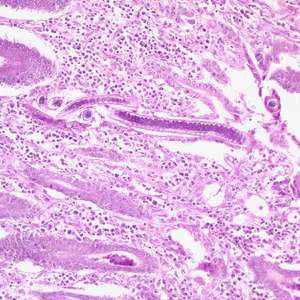

The adults of Capillaria philippinensis are very small (males: 2.3 to 3.2mm; females: 2.5 to 4.3 mm) and reside in the human small intestine, where they burrow in the mucosa

. In addition to the unembryonated, shelled eggs which pass into the environment, the females can also produce eggs lacking shells (possessing only a vitelline membrane)

, which become embryonated within the female’s uterus or in the intestine. The released larvae can re-invade the intestinal mucosa and cause internal autoinfection

. This process may lead to hyperinfection (a massive number of adult worms).

Capillaria philippinensis adult males are 2.0—3.5 mm in length and females are 2.5—4.5 mm in length. Females may contain embryonated or unembryonated eggs in utero.

The specific diagnosis of C. philippinensis is established by finding eggs, larvae and/or adult worms in the stool or in intestinal biopsies. Unembryonated eggs are the typical stage found in the feces. In severe infections, embryonated eggs, larvae, and even adult worms can be found in the feces. No valid serologic testing is available for diagnosis.